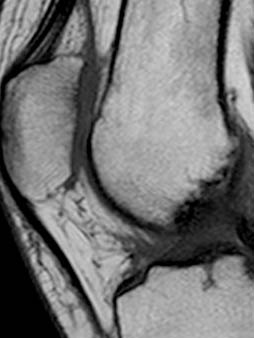

• Tutte le modalità diagnostiche disponibili: Risonanza Magnetica, TAC, Radiologia, Mammografia, Ecografia, MOC, OPT e Cone Beam, Interventistica.

• Apparecchiature di ultimissima generazione, sostituite ogni 4-5 anni.

Le apparecchiature TC ed RM utilizzate assicurano il massimo delle prestazioni (qualità di immagine e velocità di acquisizione) ormai senza più problemi di claustrofobia.